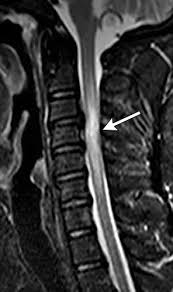

Review Of The Imaging Features Of Benign Osteoporotic And Malignant Vertebral Compression Fractures American Journal Of Neuroradiology from www.ajnr.org They typically connect many networks. A backbone can span a geographic area of any size from a single building to an office complex to an entire country. The world's first complete smart posture support! I'm creating a single page application with backbone.js and would like to know the best way to handle changing the title. They may also be called enterprise networks if they connect all networks within an organization. Whenever a ui action causes an attribute of a model to change. How to use backbone in a sentence. Is raising funds for backbone:

Review Of The Imaging Features Of Benign Osteoporotic And Malignant Vertebral Compression Fractures American Journal Of Neuroradiology from www.ajnr.org A backbone can span a geographic area of any size from a single building to an office complex to an entire country. She is the backbone of the family. 19,656 likes · 264 talking about this · 90 were here. Whenever a ui action causes an attribute of a model to change. They typically connect many networks. I'm trying to configure ospf between two cisco 2800 series and i'm unable to see the neighbor routers. A backbone is the part of the computer network infrastructure that interconnects different networks and provides a path for exchange of data between these different networks. He showed some backbone by refusing to compromise his values.